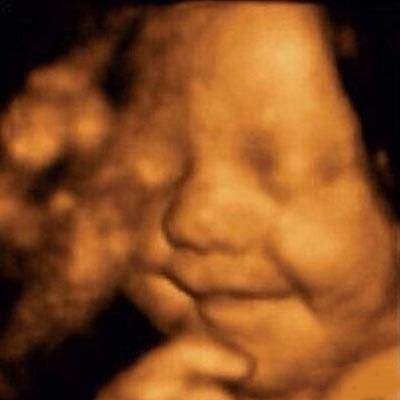

苗苗怀孕5个半月的时候去做四维彩超,她一直注视着大屏幕上宝宝的一举一动。忽然,她看到胎宝宝咧嘴笑了,这给她大大的惊喜,同时,她又很惊讶,宝宝在肚子里也会笑?常听说宝宝出生后还不会笑呢?

医生说:很正常,我们做四维彩超经常看到有宝宝笑。苗苗才知道自己是少见多怪了,而医生见的多了觉得稀松平常。

其实,关于胎宝宝在肚子里微笑,类似的报道并不少见,很多妈妈反馈过做四维时看到宝宝笑的样子,国外媒体也经常报道类似的新闻。

2003年,英国《卫报》报道,科学家用4D超声波成像系统拍到了26周宝宝微笑的图片。

2018年,英国《每日邮报》报道,一对夫妇在做四维彩超时发现宝宝咧嘴微笑,让父母感到喜出望外。

见诸各大网站的3D胎儿图像,也展示了胎儿在19周时微笑的模样,栩栩如生,惹人喜爱。

从这里看出,在做四维彩超的时候很容易捕捉到胎儿的微笑,这时不要觉得奇怪,这是胎儿正常的生理反应。